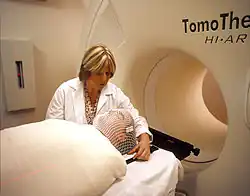

Cancer treatments can also contribute to chronic pain. Cancer treatments include chemotherapy, surgery, and radiotherapy, which are known to cause chronic pain.[18]

- Chronic post radiotherapy pain